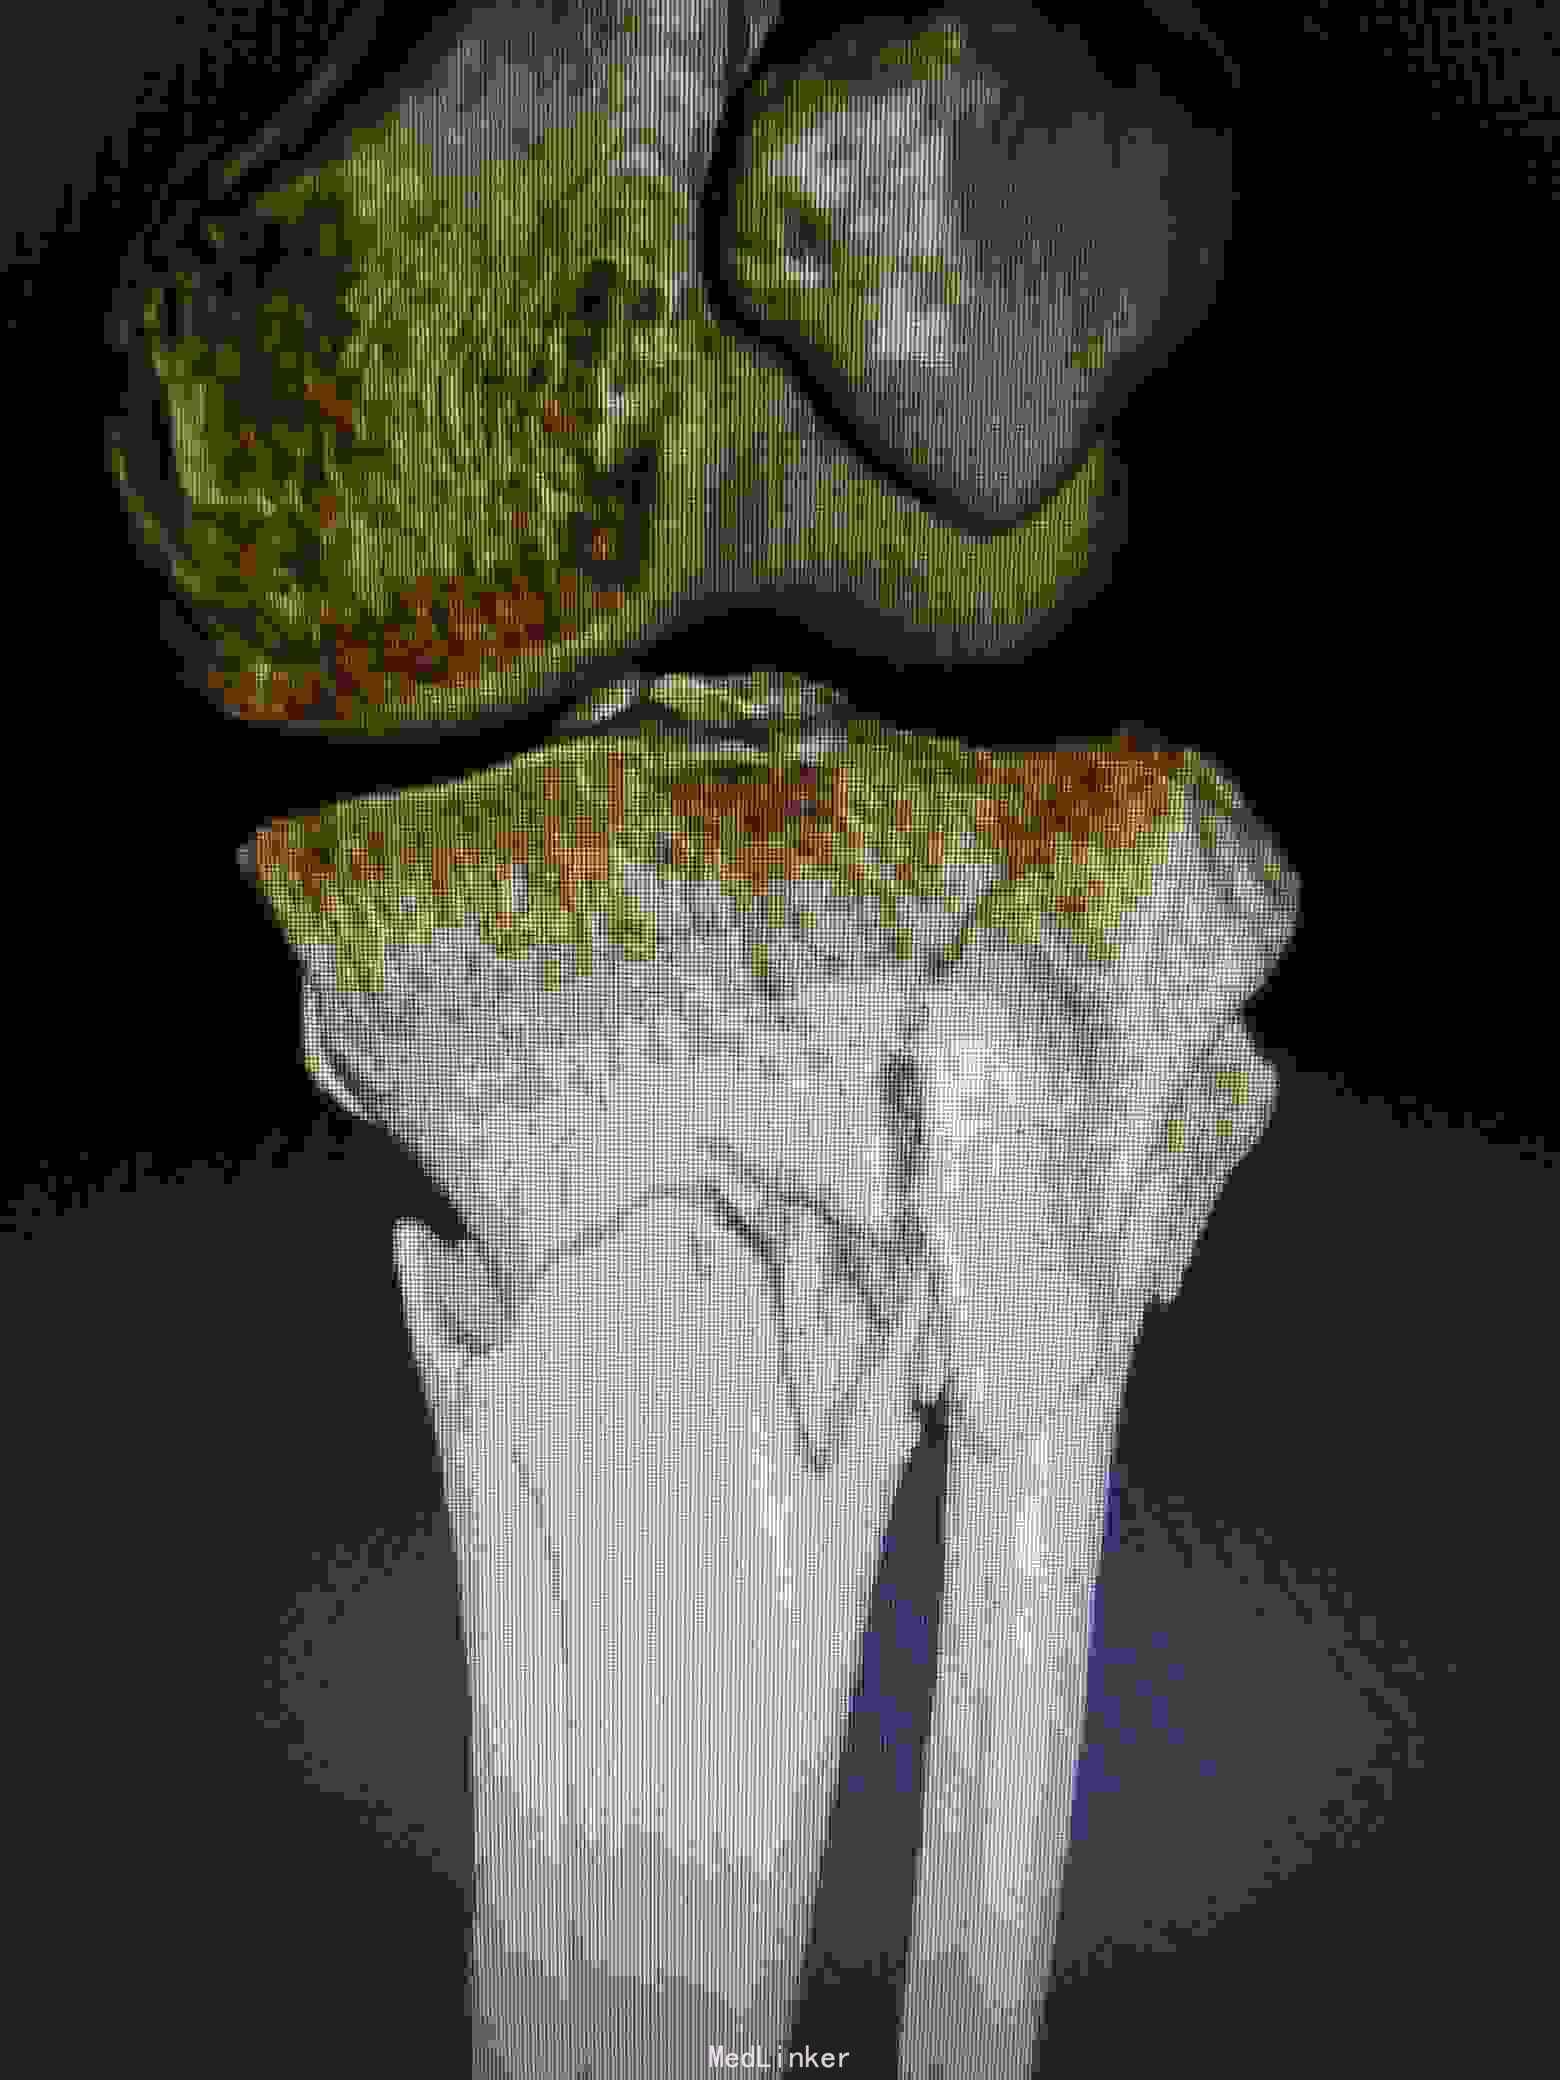

诊断:左胫骨平台粉碎性骨折(5型)。

治疗:采用俯漂体位,先行俯卧,行后内侧入路,显露胫骨平台后内侧,可以清楚显露后内侧及内侧,可以同时固定后内侧及内侧骨块。然后再漂致仰卧位,行前外切口行前外侧的钢板固定。

讨论:内外侧胫骨平台骨折,正常情况下只需在仰卧位下分别行内侧及前外侧入路进行内外侧柱的固定,但是如果骨折累计后内侧骨块,单纯内侧钢板固定仍无法稳定骨折端,这时候需要后内侧钢板的固定,仰卧位下无法清楚显露后内侧骨块,并进行固定,我们采用俯漂体位进行复位固定,俯卧下行后内侧入路,可以清楚显露后内侧及内侧骨块,同时可方便进行固定。